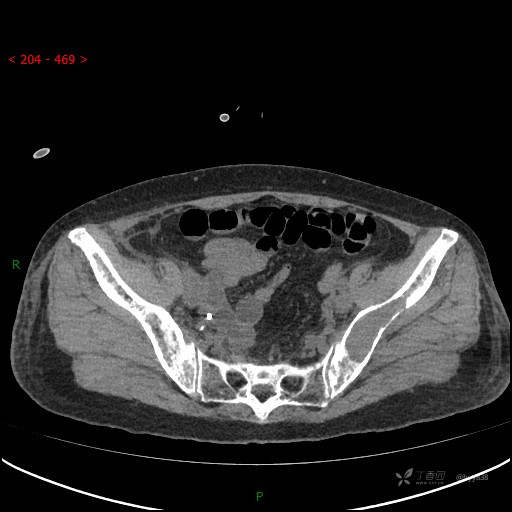

骨窗